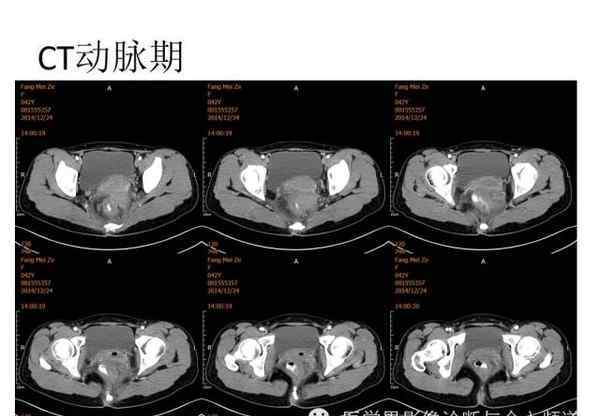

[图片图片]

[图像特征]

核磁共振平片扫描和增强扫描显示:

盆腔内可见弥漫性长T1长T2异常信号,FS-T2WI可见高信号,涉及直肠左前壁、直肠侧韧带和宫颈等。边界不清,盆腔可见条带状FS-T2WI高信号强度。注射钆喷酸葡胺后,病情明显加重。